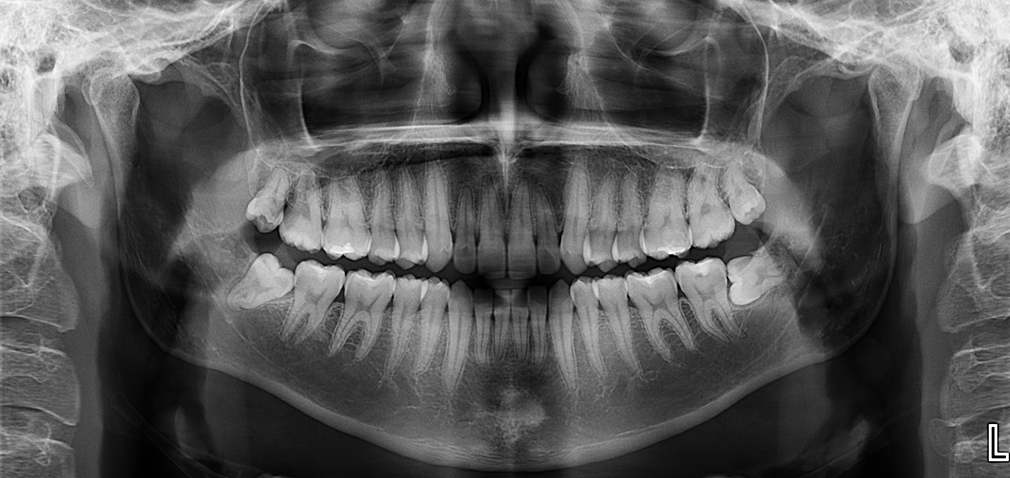

A la evaluación de la tomografía volumétrica (CBCT) en los cortes axiales (Figura 2) y transaxiales (Figura 3), se aprecia pieza supernumeraria en posición invertida localizada en zona anterior del maxilar superior, así mismo se observa disminución de la densidad a nivel coronario y reabsorción radicular externa a nivel del tercio cervical (ameloclasia).

CORTES TRANSAXIALES